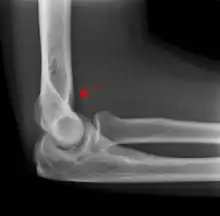

Fat pad sign: Ventral fat pad bowed and dorsal fat pad visible in a case of a nondisplaced fracture of the radius head which is not visible directly.

The fat pad sign, also known as the sail sign, is a potential finding on elbow radiography which suggests a fracture of one or more bones at the elbow. It is may indicate an occult fracture that is not directly visible. Its name derives from the fact that it has the shape of a spinnaker (sail).[1] It is caused by displacement of the fat pad around the elbow joint. Both anterior and posterior fat pad signs exist, and both can be found on the same X-ray.

In children, a posterior fat pad sign suggests a condylar fracture of the humerus. In adults it suggests a radial head fracture.

The fat pad sign is invaluable in assessing for the presence of an intra-articular fracture of the elbow. An anterior fat pad is often normal. However a posterior fat pad seen on a lateral x-ray of the elbow is always abnormal. The patient will be unable to flex their elbow and requires orthopaedic input.[2]

The posterior fat pad is normally pressed in the olecranon fossa by the triceps tendon, and hence invisible on lateral radiograph of the elbow.[3] When there is a fracture of the distal humerus, or other pathology involving the elbow joint, inflammation develops around the synovial membrane forcing the fat pad out of its normal physiologic resting place. This is visible as the "posterior fat pad sign" and is often the only visible marker of a fracture, particularly in the pediatrics population.